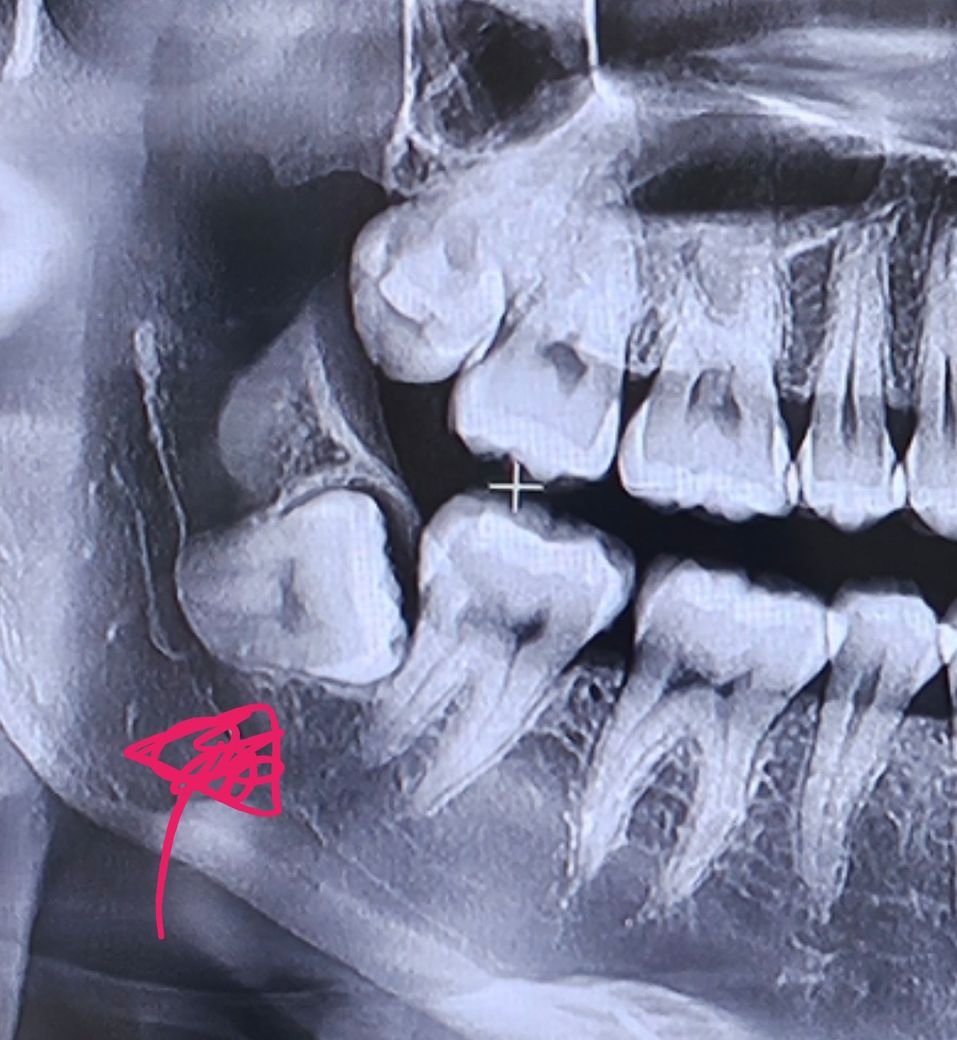

잇몸 아래 매복된 사랑니 빼야 할까요?

잇몸 아래 사랑니가 매복되어 있어요. 잇몸 위면 이물질이 낄 수 있기 때문에 빼야 할 것 같은데 지금은 통증도 전혀 없고 잇몸 아래라 굳이 안 빼도 될 것 같아서요.

문의하고 싶은 자리의 사랑니는 표시해 두었습니다. 위에 있는 사랑니는 뺄 예정이에요. 확인 부탁드리겠습니다 :)

사진으로 봤을 때 사랑니는 완전히 매복되어 있는 것으로 보입니다. 매복돼 있는 상태에서 특별한 문제를 발생시키고 있지는 않기 때문에 굳이 발치를 할 필요는 없을 것으로 생각됩니다. 자세한 확인을 위해서 치과에서 진료를 받으 전화번호는 것을 권유 드립니다.

매복 사랑니는 방향이 비뚤어져 나오면서 바로 앞 어금니를 상하게 하기에 가급적 빠른시일내에 발치를 하는 것이 좋습니다. 통증 없다고 두면 바로 앞 어금니가 서서히 상하게 되어 나중에는 두개의 치아를 모두 발치가 필요로 될수 있습니다

잇몸뼈 아래로 위치하고 옆 치아에 겹쳐있지는 않을 것으로 보이기 때문에 꼭 뽑아야 하는 상황은 아닐듯 합니다